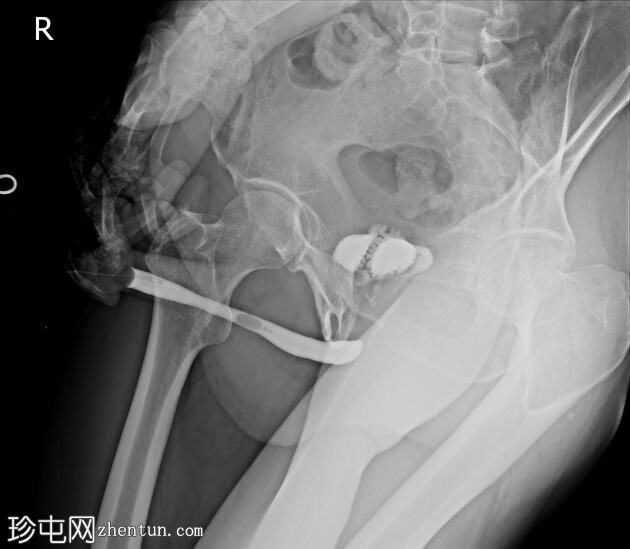

排尿困难。既往有膀胱癌病史及根治性膀胱切除术。

前列腺部、膜部、球部及阴茎部尿道均正常。

造影剂经尿道注入,开始充盈具有肠袢特征的新膀胱。

该患者确诊为移行细胞癌后行膀胱切除术。治疗方案包括根治性膀胱切除术及新膀胱重建术。